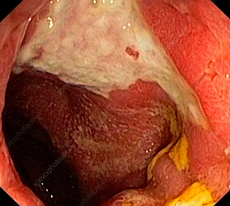

Κολονοσκόπηση. Ευδιάκριτα ευρήματα ισχαιμικής κολίτιδας (Ευγενική παραχώρηση Dr. V. Penopoulos)